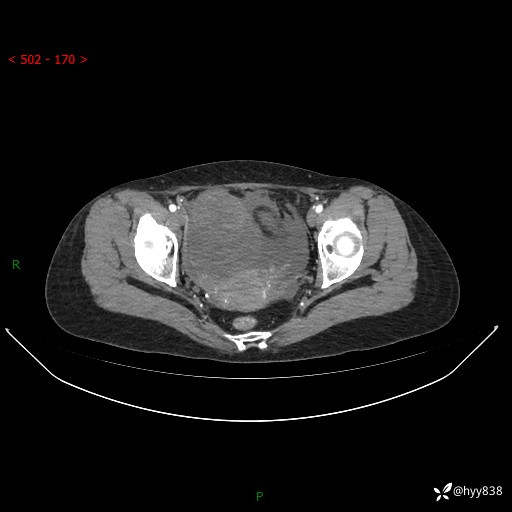

腹盆CT平扫

增强